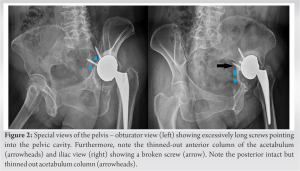

Obturator and iliac views of the pelvis (Fig. 2) were taken, which revealed all acetabular screws to be intrapelvic, far beyond the safe zone. One screw had broken due to prosthetic migration. Three dimensional computed tomography (Fig. 3) confirmed our findings.

Acetabular bone loss was classified by Paprosky classification as Type 3A that is, superior and lateral migration ≥3 cm with intact medial support (Kohler’s line). To assess the proximity of these screws with the intrapelvic vasculature, a computed tomographic (CT) angiography of the pelvis with the lower limb was performed which, to our surprise, revealed one screw tip being interposed between the external iliac artery and vein (Fig. 4 and 5) and a catastrophic vascular injury waiting to happen.